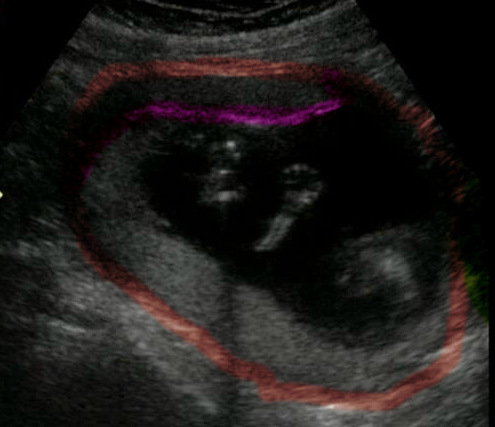

Hi ladies, had a scan today at 6 weeks

Scan: transvaginal

Plane: sagital

Orientation: my right side is on the right and my left side is on the left of the picture.